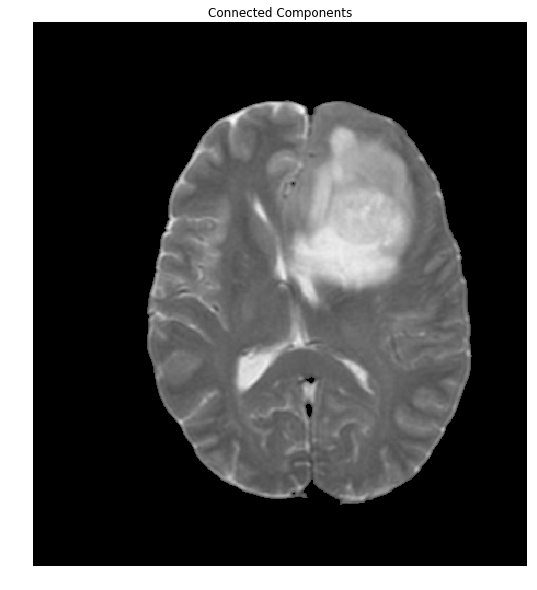

Extracting the Brain

The overlap of the brain (shown in red) with the mask is so perfect, that we'll stop right here. To do so, let's extract the connected components and find the largest one, which will be the brain.

ret, markers = cv2.connectedComponents(thresh)

#Get the area taken by each component. Ignore label 0 since this is the background.

marker_area = [np.sum(markers==m) for m in range(np.max(markers)) if m!=0]

#Get label of largest component by area

largest_component = np.argmax(marker_area)+1 #Add 1 since we dropped zero above

#Get pixels which correspond to the brain

brain_mask = markers==largest_component

brain_out = img.copy()

#In a copy of the original image, clear those pixels that don't correspond to the brain

brain_out[brain_mask==False] = (0,0,0)

ShowImage('Connected Components',brain_out,'rgb')